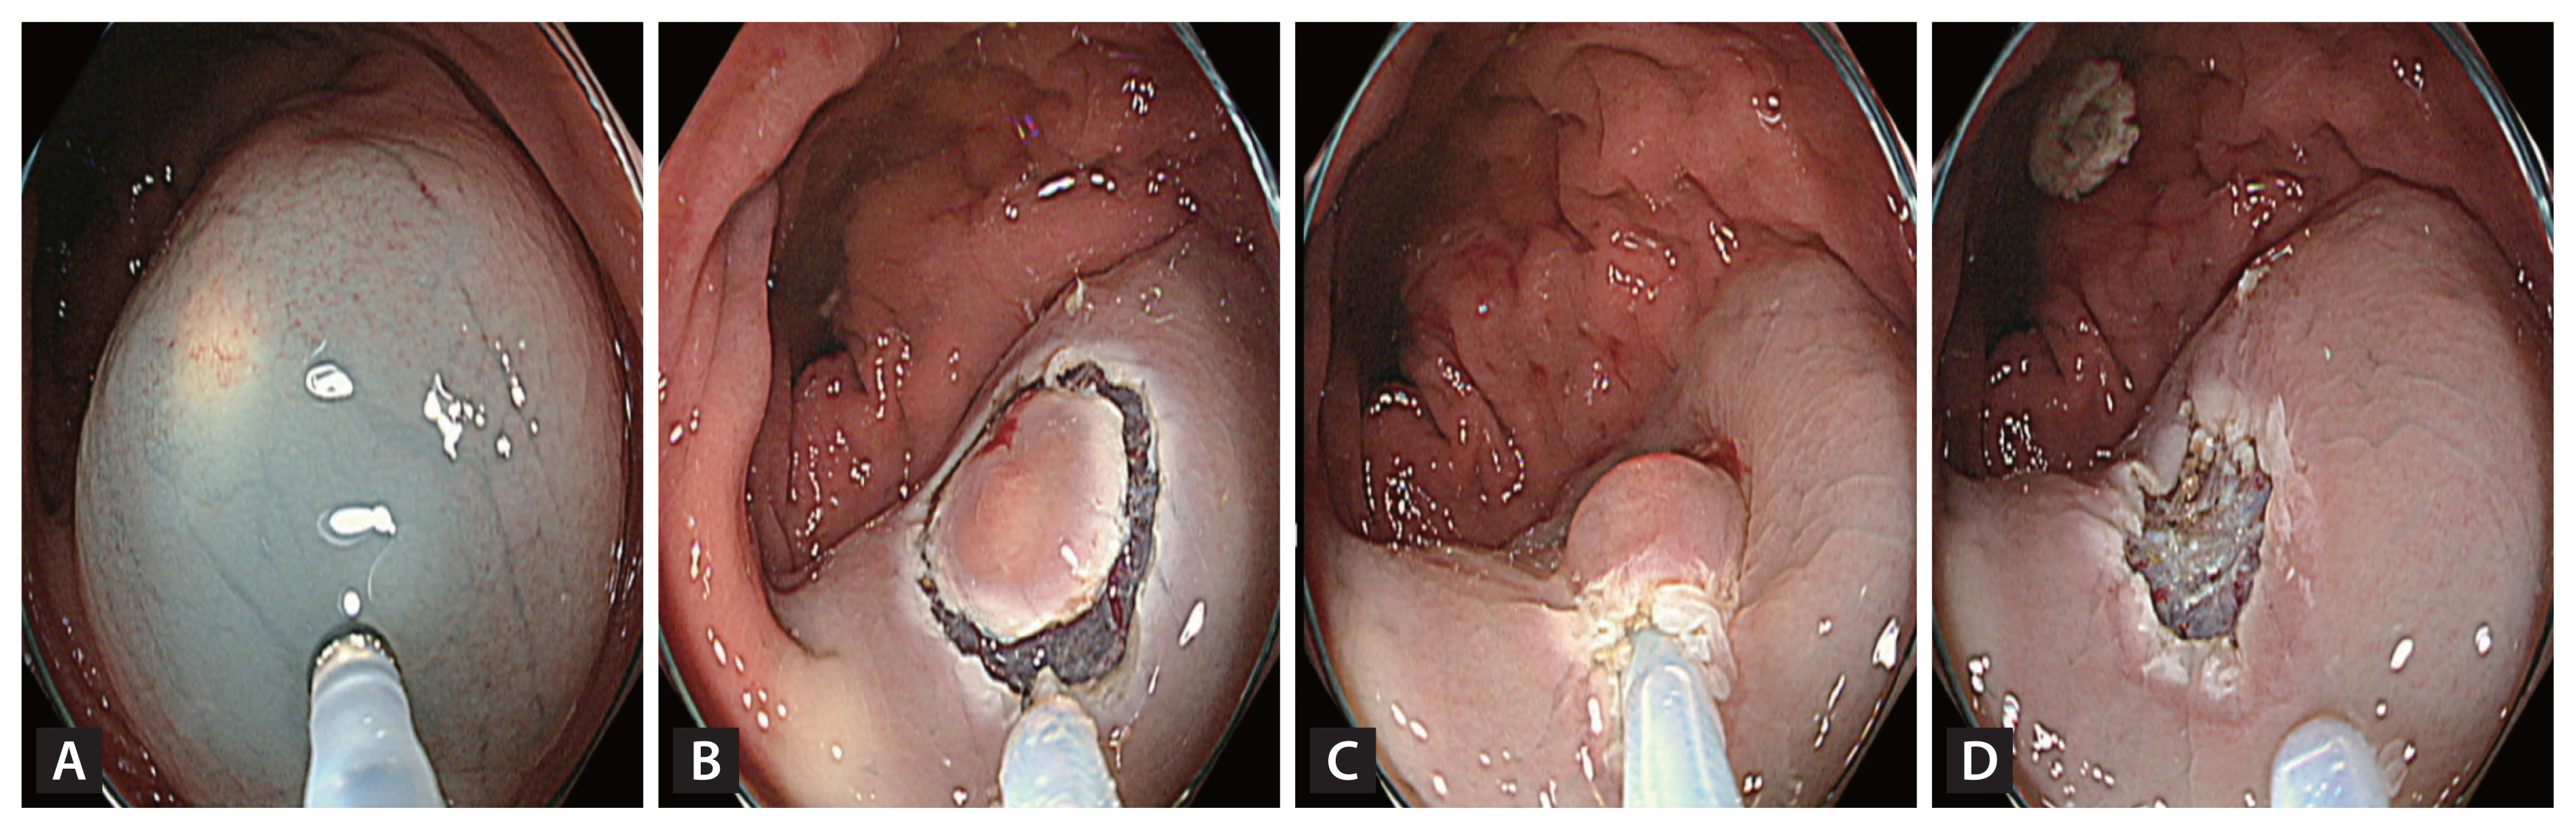

A high-definition colonoscope (CF-HQ 290 EVIS LUCERA ELITE; Olympus Corporation, Tokyo, Japan) with a transparent cap and 13-mm oval type stiff snare with a 0.42-mm wire diameter (Captivator; Boston Scientific, Marlborough, MA, USA) were used for both the methods. The EMR-P procedure was performed as follows: a mixture of normal saline, 1:100,000 epinephrine and indigo carmine were injected submucosally to lift the lesion. Using the tip of the snare, a fully circumferential incision was made around the lesion. Next, the lesion was snared along the circumferential incision and resected with an electric current (Fig. 1). For the Tip-in EMR procedures, the same submucosal solution was injected around the lesion, and a mucosal slit of 2–5 mm in width was made approximately 5 mm from the proximal edge of the lesion [27]. Next, the tip of the snare was anchored into the mucosal incision, and the snare was slowly opened. Furthermore, the snare was gently pressed towards the anchor site to maintain the width of the snare and ensure a leverage effect for the lesion [27]. The snare sheath was pressed downward to entrap the deep submucosal tissue together with the lesion [27]. Finally, the captured lesion was resected using the electric current (Fig. 2).

Images of Tip-in endoscopic mucosal resection (A) After injecting a submucosal solution, create a slit using the snare tip. (B) Fix the snare tip onto the slit and expand the snare to capture the lesion extensively. (C) Close the snare with an adequate margin. (D) Image after resection.